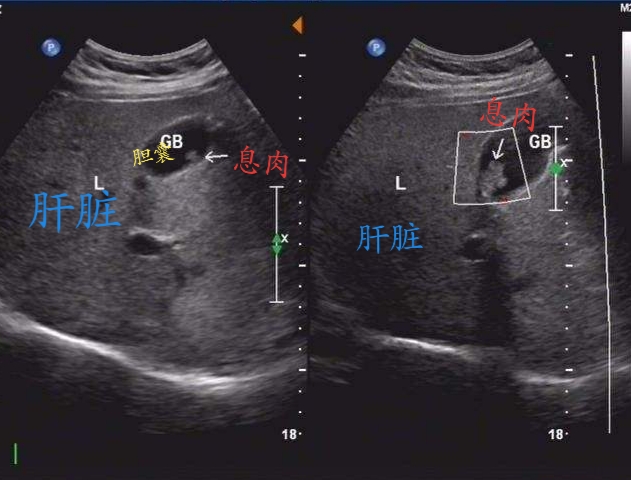

胆囊息肉彩超

超声影像 胆囊息肉又称胆囊息肉样病变 可分为良性或恶性病变

科普|超声:胆囊息肉的"侦察兵"